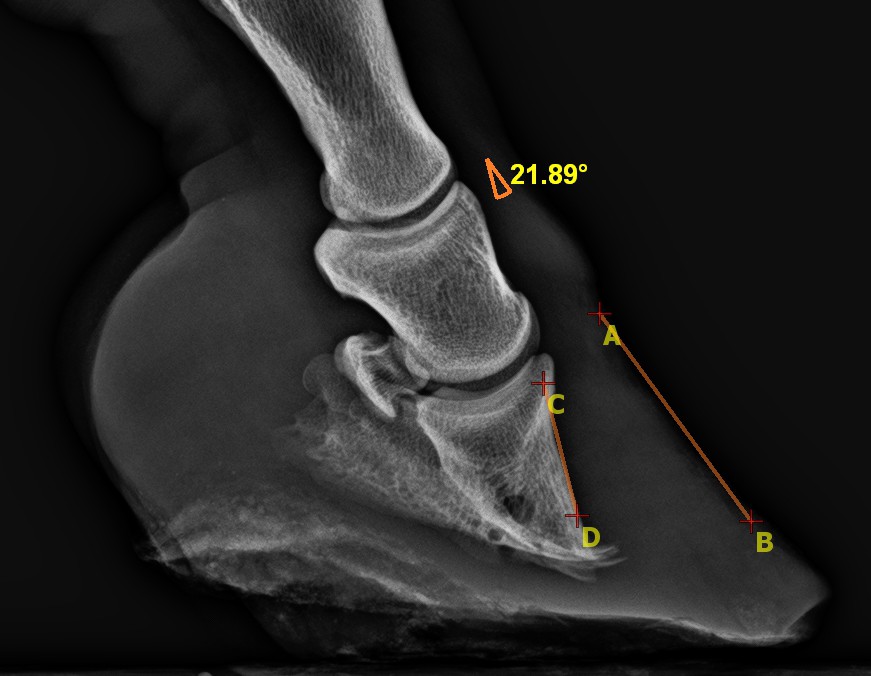

Igen nagyfokú, régi, 21 fokos elcsavarodás. A patacsont hegye, a rá nehezedő nyomás miatt átalakult, „felhajlott” (D betű alatt).